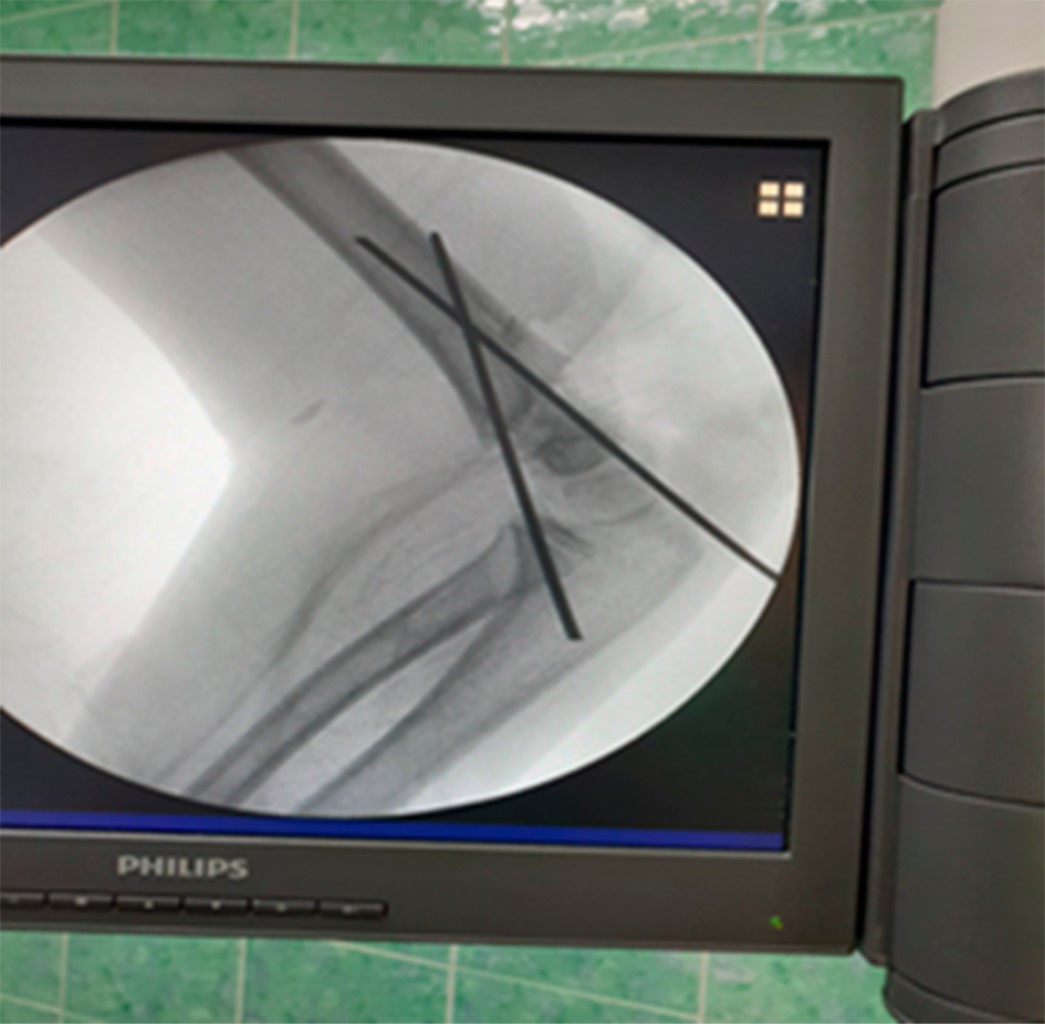

Treatment of supracondylar fractures of humerus in children with percutaneous internal fixation versus reduction without internal fixation

Introduction: Supracondylar fractures of humerus are the second most frequent type of fractures in children. Objective: To describe the results of the treatment, the patients according to age, sex, complications, and final results. Material and methods: A retrospective descriptive study was conducted in patients with supracondylar fractures of humerus during the years 2018-2019. Absolute frequencies and percentages were calculated. Results: Fractures were more frequent in males (69.6%) and in the age group of six to 10 years for both sexes. 60.8% of the fractures were treated with reduction plus internal fixation with Kirschner needles, in the group with internal fixation type IV predominates and in the group that does not need internal fixation predominate type I, the most frequent complication was the loss of reduction in the group that was not fixed with needles. Better results were obtained when the reduction was performed combined with internal fixation (91.2%). Conclusions: Fractures predominated in the male sex and in the age group of six to 10 years, the reduction was more frequent more internal fixation with Kirschner needles, in the group with internal fixation predominates type IV, predominated the loss of reduction in the group that was not fixed with needles. Better results were obtained when reduction was performed combined with internal fixation.

Figure 1